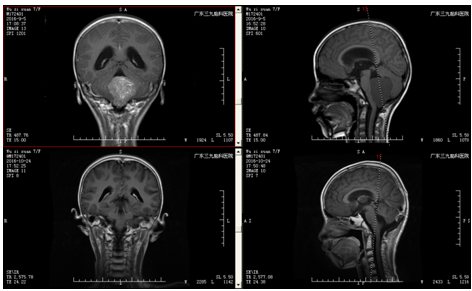

患儿吴某,女,7岁,反复头晕头痛伴恶心呕吐、行走不稳一周,遂就诊当地医院行头颅MR示:四脑室肿瘤,脑疝形成,脑阻性脑积水。为求进一步治疗,转入我院治疗。完善术前准备后,行四脑室肿瘤切除术,手术由神经外二科主任林涛主刀完成,术中肿瘤全切。病理:髓母细胞瘤,术后患者神志清楚,肢体活动良好。

广东三九脑科医院神经外二科林涛主任介绍:第四脑室是一个非常关键的解剖区域,腹侧毗邻桥脑、延髓等脑干结构,又是脑室系统内脑脊液循环通路的最后环节。由于瘤体周围有重要的神经、血管组织,故手术彻底切除肿瘤难度较大。